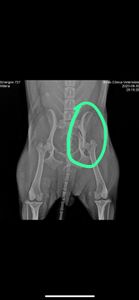

Socorri essa mocinha que foi atropelada em frente ao Max atacadista em Toledo não vi que carro foi somente a cadelinha tentando se erguer no meio da pista em direção ao canteiro central, e as patinhas de trás já não mexiam. Levamos até a clínica Bless e depois de exames veio a notícia da fratura de pelve e necessidade de cirurgia para voltar a andar, não pude fechar os olhos para esse ser indefeso, como não localizamos o dono autorizamos a cirurgia que junto com estadia e mediação está em R$2.800,00 até o momento.